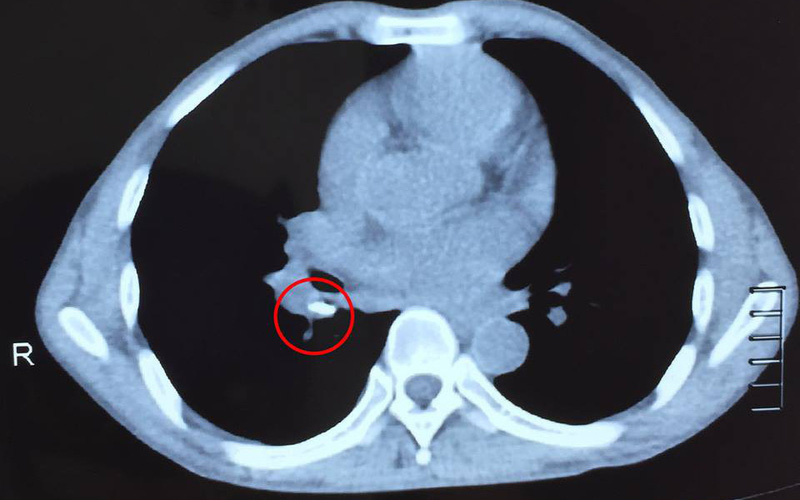

Bệnh nhân nhanh chóng được đặt nội khí quản kiểm soát đường thở. Chụp sọ não ghi nhận khối máu tụ ngoài màng cứng đỉnh phải, lượng rất nhiều, chèn ép nhu mô não, gây thoát vị não một trong những dấu hiệu nặng gây nguy kịch đến tính mạng bệnh nhân.